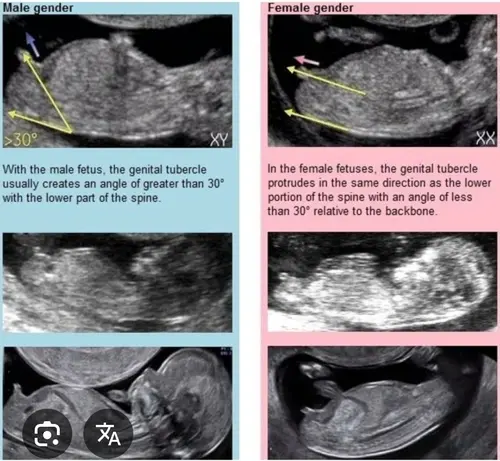

Ik denk meisje. Bij jongen zou het volgens mij echt meer naar boven moeten steken.

Jaaa ik raak zoo zenuwachtig hahaha maar dat heb je met die theorie毛n natuurlijk. Ik zie zelf idd ook meisjes nub

Het geslacht is niet helemaal duidelijk te zien, dus het zou zo goed een meisje als jongen kunnen zijn. Maar ik gok een meisje! 馃

Hahah dat zou je zeggen he maar het is een beetje een onduidelijke positie waarbij het niet goed te zien is

Jaa dat zei de verloskundige idd maar ik denk idd dan veen ervoor. Heb 1 waar je hem helemaal ziet. Theorie毛n blijven lastig 馃き馃槀